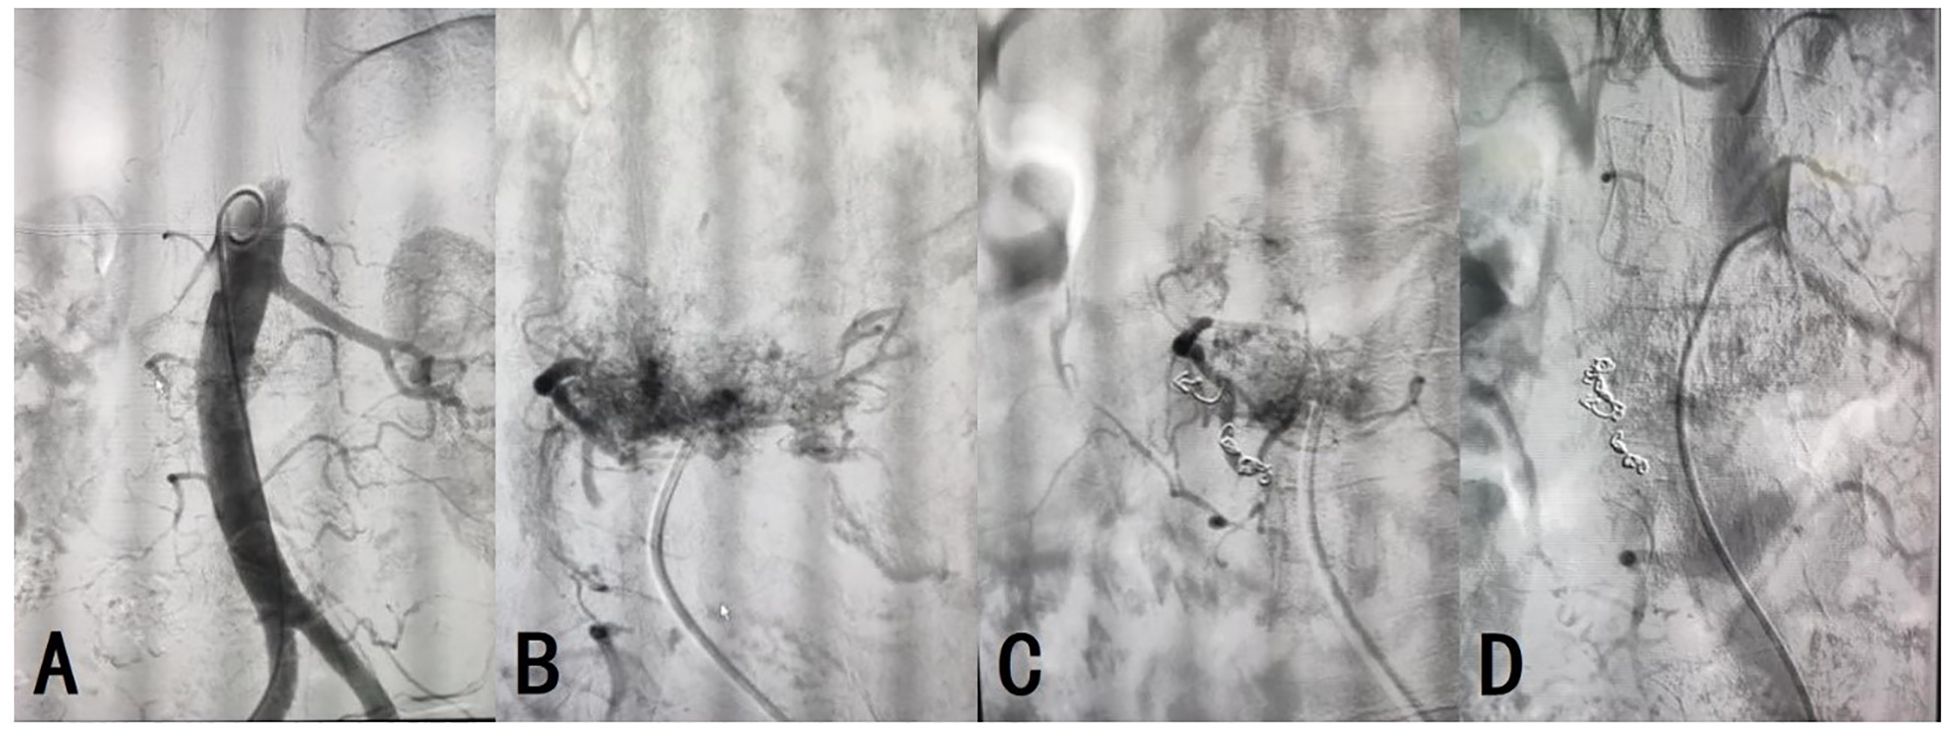

On day 2 post-admission, aortic and lumbar artery angiography and embolization were performed under local infiltration anesthesia. The patient was placed in the supine position and the surgical area was routinely disinfected. Using the Seldinger technique, the right common femoral artery was retrogradely punctured and a 6F catheter sheath was inserted. A 0.035 guidewire and a 5F pigtail catheter were used to guide the catheter into the proximal abdominal aorta. Angiography revealed abnormal abdominal aorta staining at L2, suggesting a hemangioma approximately 5×6 cm in size, primarily fed by the right first lumbar artery. Following C2 catheter, MPA catheter, and 0.035 guidewire entry, a microcatheter and microguidewire were introduced into the right first lumbar artery to introduce five 3×20 mm coils and two 5×20 mm coils for embolization. Follow-up angiography confirmed the disappearance of the abnormal right first lumbar artery staining and successful embolization (Figure 3). The guidewire and catheter sheath were withdrawn, and the puncture site was closed using a vascular closure device with local pressure dressing. The operation was uneventful, and the patient returned to the ward in good condition.

Figure 3

Four X-ray images labeled A to D show different stages of a cerebral angiography procedure. A shows the initial arterial structure. B displays a cluster of tangled vessels. C and D show coiling embolization with visible coils reducing blood flow in the affected vessels.

Figure 3. (A) Technical success of the arterial angiography was achieved. (B–D) The embolization of AVH was successful, with resolution of the abnormal vascular staining.